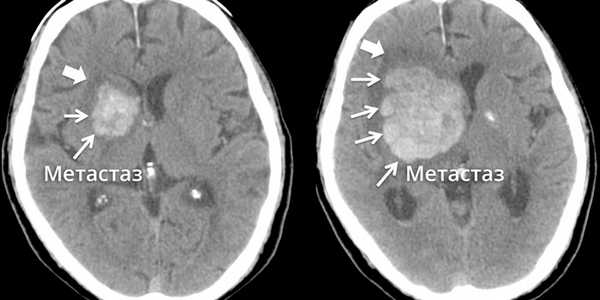

Метастазы в головном мозге.

Метастаз в головном мозге в динамике

«Золотой стандарт» в диагностике метастатического рака головного мозга — магнитно-резонансная томография (МРТ). Во время этого исследования получают изображения внутренних структур тела, используя сильное магнитное поле. По снимкам врач может судить о количестве, размерах, расположении метастатических очагов.